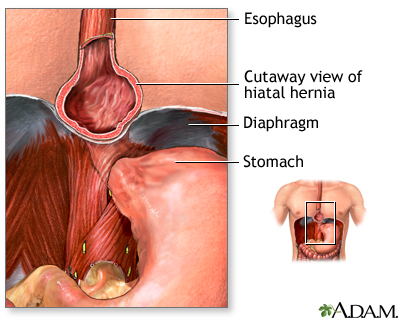

Heartburn is more likely if you have a hiatal hernia. A hiatal hernia is a condition which occurs when the top part of the stomach pokes into the chest cavity. This weakens the LES so that it is easier for acid to back up from the stomach into the esophagus.